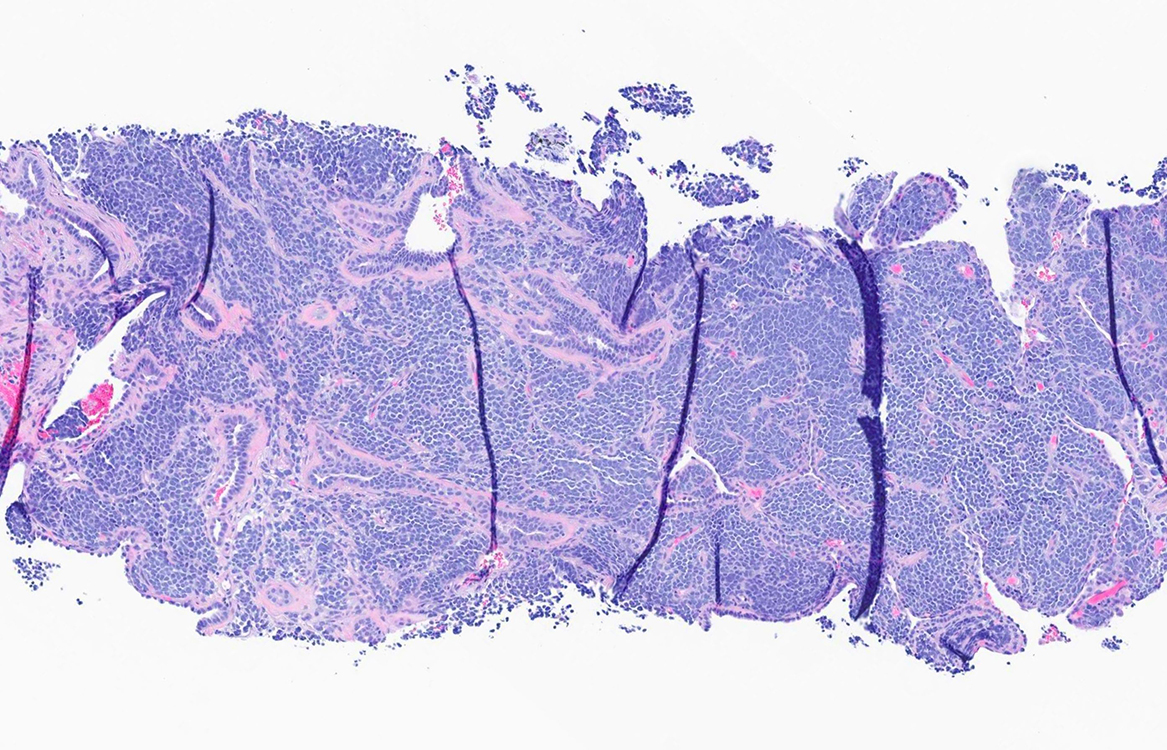

Figure 1 (H and E 5x)